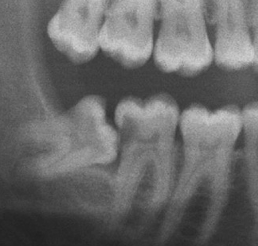

Q

Darkening of the root where crossed by the canal